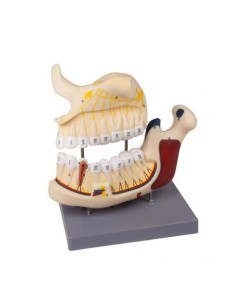

Erler Zimmer, modello anatomico per spiegare la corretta igiene orale D217

Modello di lingua e denti, grandezza naturale, 4 parti Erler Zimmer EZ-D443